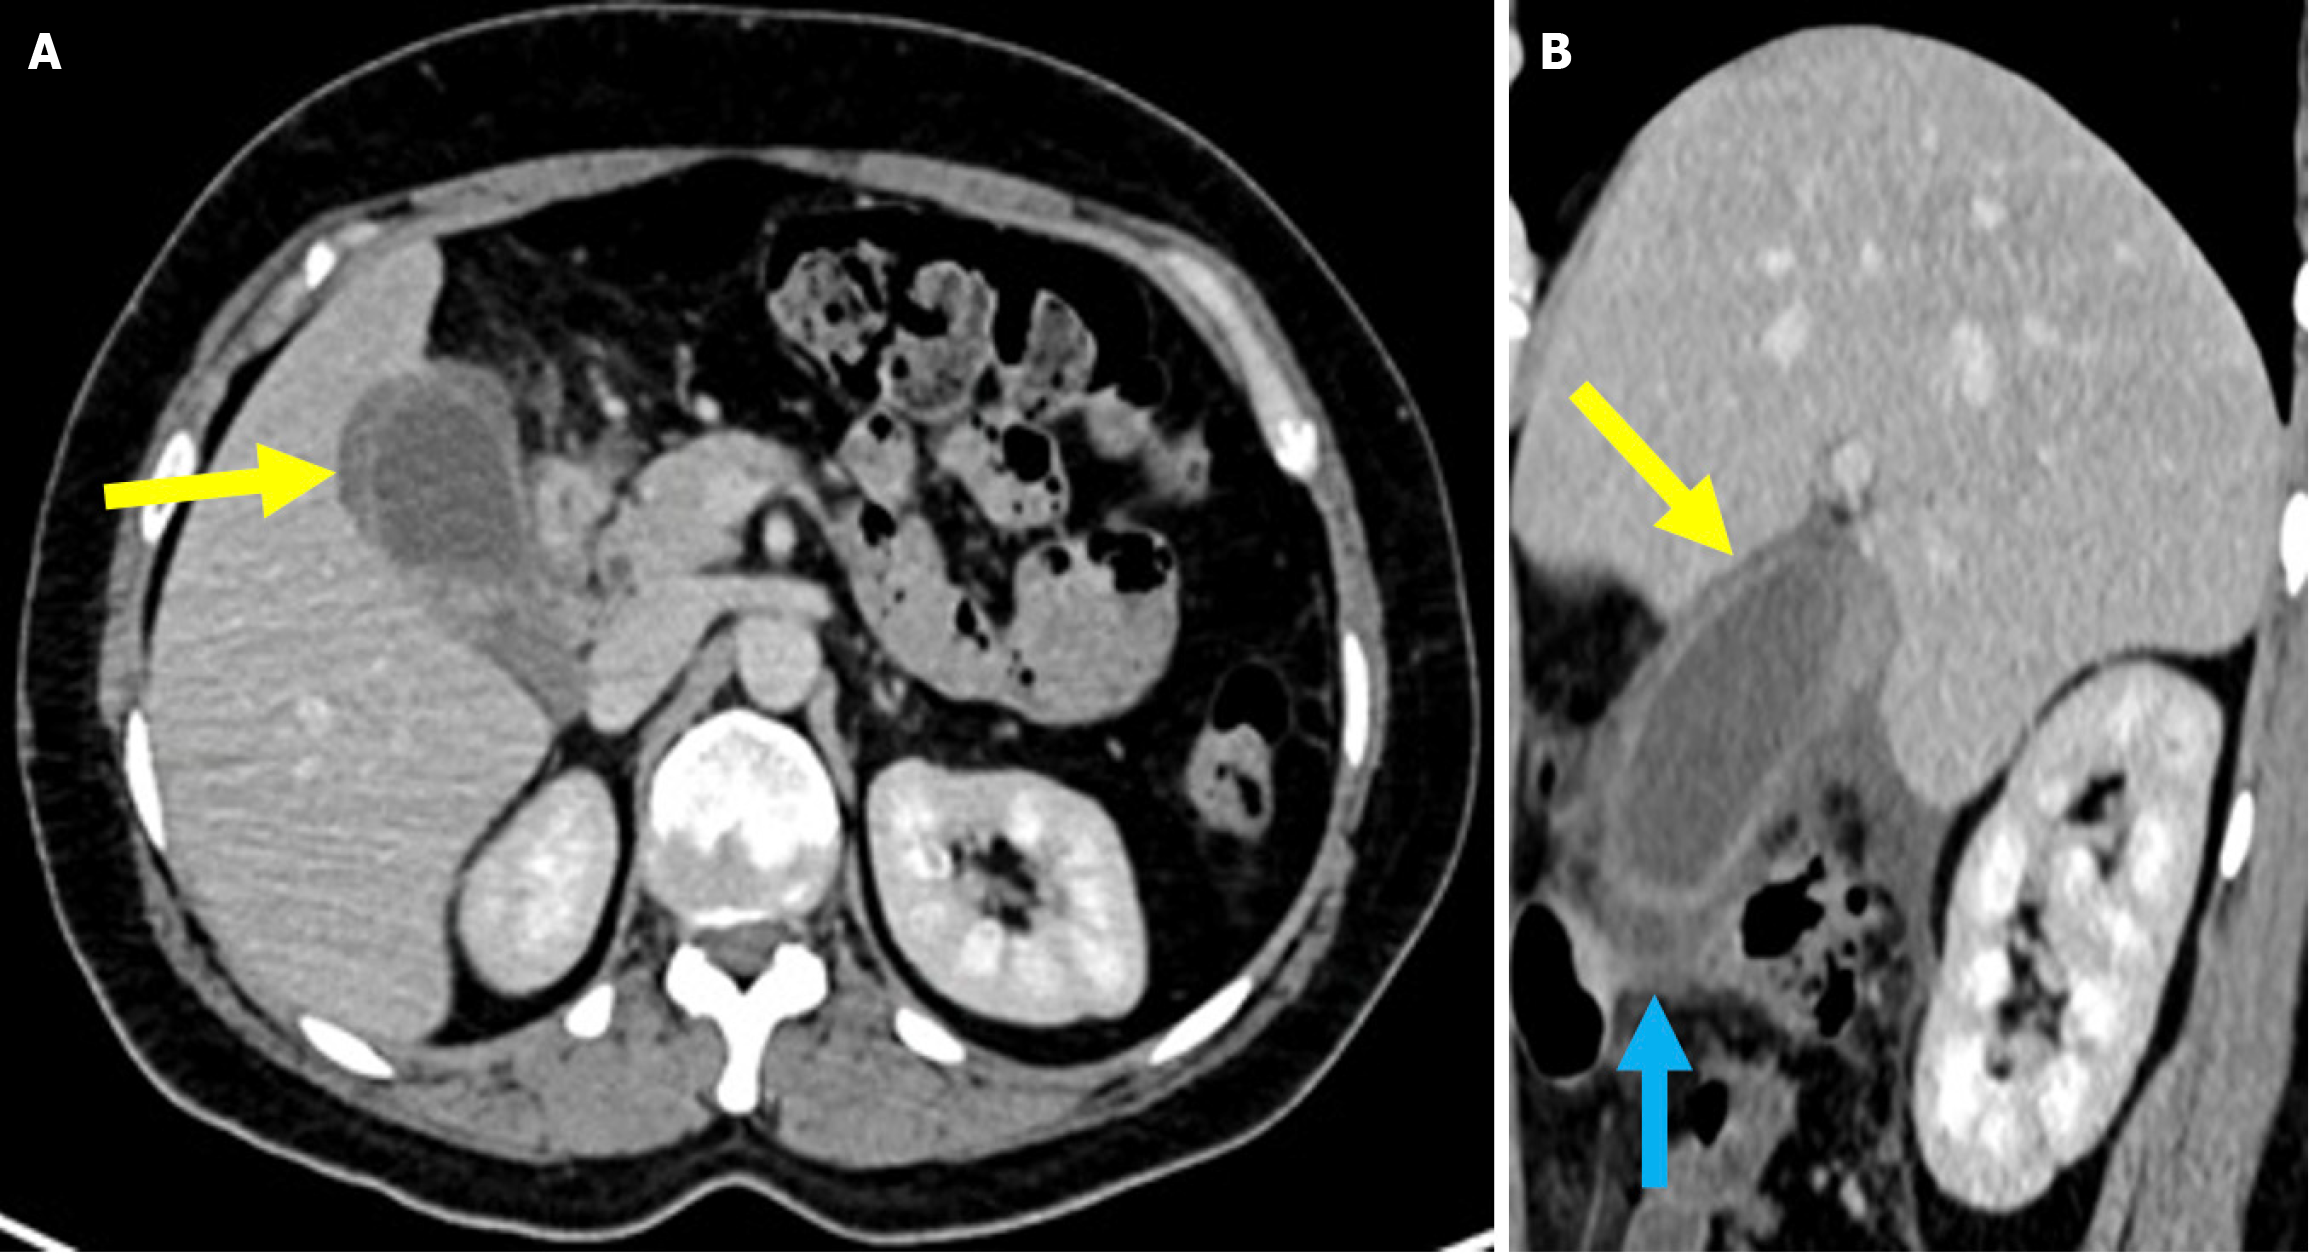

A subcapsular hematoma resulting from the tearing of vascular or biliary structures during wire manipulation or balloon dilation may occur. In addition pseudoaneurysms can develop from irritation or erosion of adjacent vessel walls by biliary stents. These complications may require surgical or angiographic intervention (Figure 11)[63-66].

Figure 11

Figure 11  Hepatic pseudoaneurysm. A and B: Axial (A) and coronal (B) computed tomography (CT) angiography in the arterial phase. C: Digital subtraction angiography during therapeutic intervention. A 63-year-old female patient presented with a rapid drop in hemoglobin and melena following the removal of a previous plastic stent. The patient developed progressively worsening periumbilical abdominal pain and exhibited signs of hypovolemic shock. Arterial phase CT angiography revealed a pseudoaneurysm originating from the left hepatic artery (yellow arrows). The digital subtraction angiography image showed successful embolization of the pseudoaneurysm with coil placement (blue arrow).